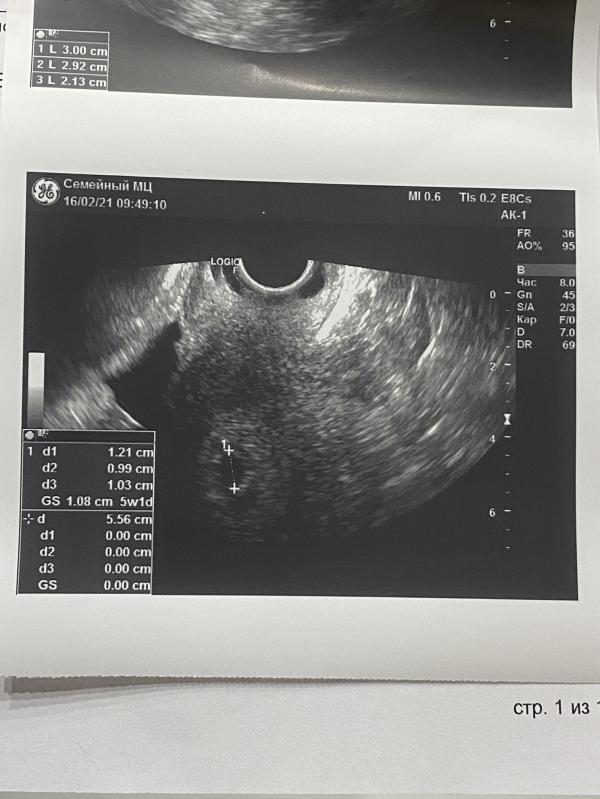

Сходили на узи😊🙏🏼🤞срок по узи 5.1, плодное яйцо в матке 🙏🏼но эмбриона пока не видно. Решено с врачом, чтобы +100500 раз не лазить туда, сделаем через дней 10-14, за одно сердечко 💓 послушаем и размеры эмбриончика посмотрим 🙏🏼🤞

Ситуация как у меня на сроке 5 недель, через две недели и эмбрион и сердечко, растите, лёгкой беременности и родов в срок🙂